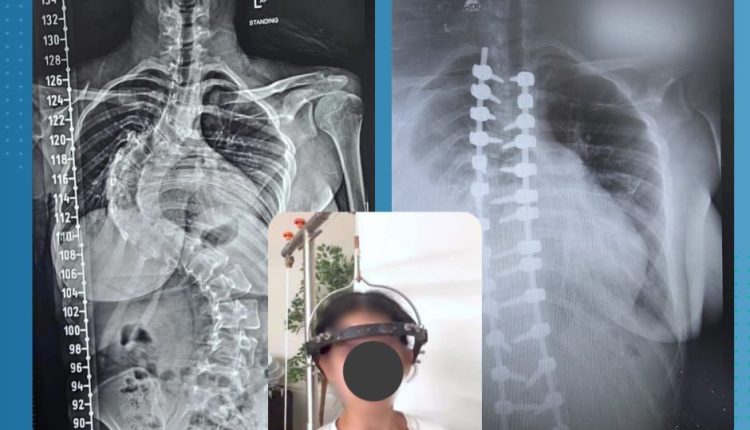

تمثّل في معالجة حالة جنف شديد ومعقّد باستخدام تقنية السحب التدريجي Halo Traction لمدة ستة أسابيع، تلاها إجراء عملية جراحية دقيقة لتصحيح العمود الفقري، وذلك لفئة من الحالات التي تُعد من الأكثر تعقيداً وخطورة على مستوى جراحة العمود الفقري،حيث انه وصلت الحالة بدرجة انحراف :

• 110 درجات في المنطقة الصدرية

• 90 درجة في المنطقة البطنية (القطنية – الصدرية السفلية)

وهي زوايا تعتبر من أعلى درجات التشوّه التي تستدعي تدخلاً متعدد المراحل بسبب خطرها الشديد على النخاع الشوكي والأعضاء الحيوية.

جرى تطبيق جهاز Halo Traction بهدف تقليل درجة الانحراف تدريجياً وتخفيف الضغط على النخاع الشوكي، مما يهيّئ العمود الفقري لعملية التصحيح النهائية بأمان أكبر. وقد استمرت هذه المرحلة لمدة ستة أسابيع، تخللها مراقبة دقيقة ومتابعة طبية حثيثة.